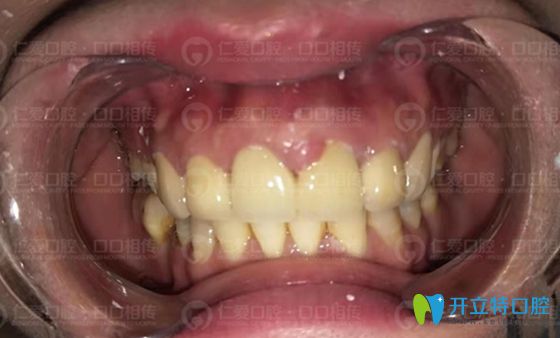

顧客在<!--<i data=20240703-sp></i>-->口腔修復(fù)烤瓷牙術(shù)前照

經(jīng)過和劉先生的詳細(xì)溝通之后,為劉先生上頜的六顆前牙重做成二氧化鋯全瓷牙套。由于劉先生整體牙齒發(fā)黃,全瓷牙冠也選了和其他牙齒匹配的色號,看起來比較自然,不突兀。